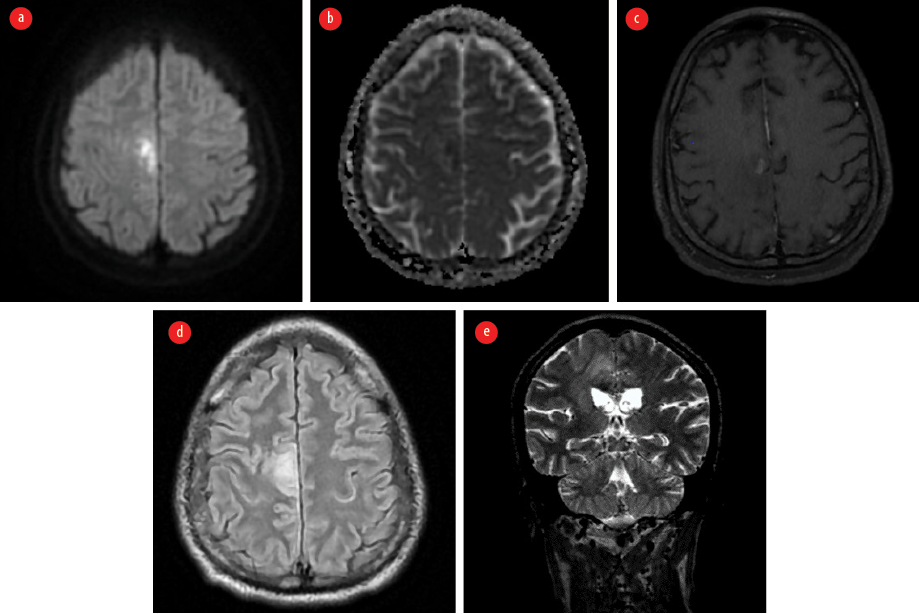

However, one month later, while still on oral co-trimoxazole, the patient presented with fever, headache, recurrent left focal motor seizures, and eventually fell into a coma, necessitating mechanical ventilation. Repeat contrast-enhanced MRI of the brain revealed irregular, streak-like enhancing areas with surrounding edema, originating in the precentral gyrus of the right frontal lobe and extending to the posterior limb of the internal capsule and the midbrain via the cerebral crus. It was noted to cross the midline at the level of the red nucleus. This irregular enhancement was also noted to involve the superior cerebellar peduncle [Figure 3].

Figure 3: Contrast-enhanced MRI of the brain taken following the first relapse. (a) Axial section shows irregular streak-like enhancing areas starting at the right prefrontal gyrus; (b) Axial section shows extension of enhancement along the right posterior limb of the internal capsule. (c) Axial section shows involvement of the midbrain with crossing of the midline. (d) Sagittal section indicates entry into the cerebellum via the left superior cerebellar peduncle.